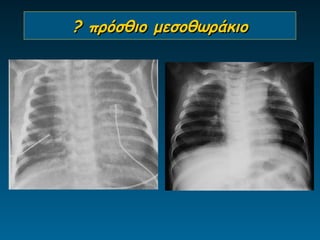

? πρόσθιο μεσοθωράκιο

Έφηβοι

8 μηνών, βρογχιολίτις

14 μηνών, Εμπύρετο προ 2μήνου, παθολογική α/α

θώρακος, επανέλεγχος

Θύμος

•     Διεύρυνση ανώτερου πρόσθιου

μεσοθωρακίου

•     Ευγενική τριγωνική δομή

•     Ακεραιότητα πνευμονικών δομών

•     Παιδιά έως 6 ετών

• Εναλλακτικά της α/ας ΥΧ       -ΥΤ-ΜΤ